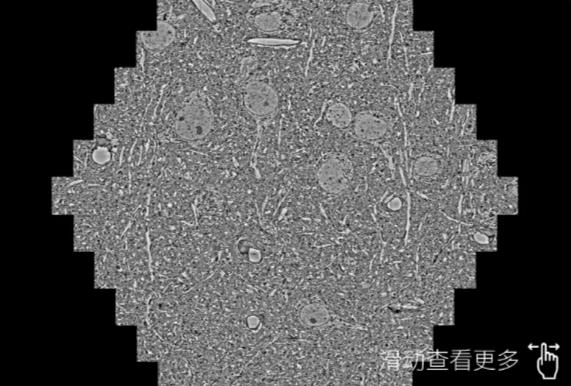

鼠脑切片。左图使用驻马店蔡司驻马店扫描电镜MultiSEM706对165μmx143pm面积区域成像,耗时仅需1.5秒。右图为鼠脑切片中30μm区域放大效果。样品由芝加哥大学B.Kasthuri提供。

使用蔡司高速驻马店扫描电镜MultiSEM对1mm²人脑皮层组织进行高分辨成像,并对其中的各种细胞结构进行三维重构分析。左图展示了2x3mm²组织平面中锥体神经元的三维重构效果。右图显示了局部体积神经元三维重构。图像由哈佛大学chtman实验室提供,渲染图由D. Berger 制作。